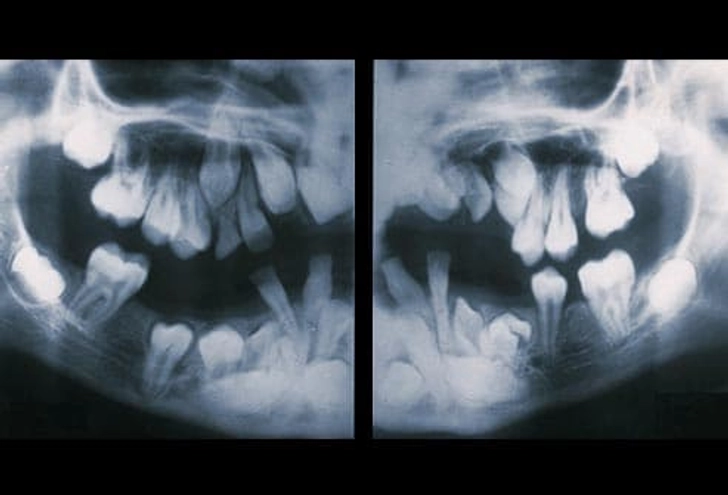

۵. دندان نهفته (Impacted Teeth)

دندانهای دائمی که درست رویش نمیکنند «نهفته» نام دارند. این حالت معمولاً وقتی رخ میدهد که دندان به دندان کناری، استخوان یا بافت نرم گیر کرده باشد. اگر مشکلی ایجاد نکند، ممکن است دندانپزشک توصیه کند همانطور باقی بماند. اما در صورت درد یا احتمال بروز مشکل، دندان توسط جراح فک و صورت خارج میشود.

۱۳. مشکلات دندان عقل

بیشتر افراد (۹۰٪) حداقل یک دندان عقل نهفته دارند. این دندانها میتوانند باعث پوسیدگی، آسیب به دندانهای کناری و بیماری لثه شوند. رویش دندان عقل معمولاً بین ۱۷ تا ۲۵ سالگی رخ میدهد. دندانپزشک باید روند رشد را پیگیری کند و در صورت مشکل، دندان کشیده میشود.